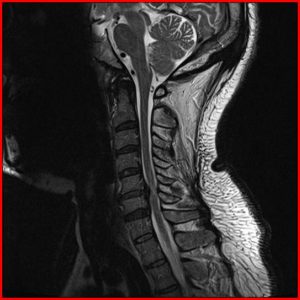

CERVICALSPONDYLOSIS AND SLIP DISC

Cervical spondylosis is a process of wear and tear of the discs between our neck bones. Due to this wear and tear, the water content in the disc decreases. As a result of this, the normal load bearing capacity of the disc is compromised resulting in neck pain. Mostly, cervical spondylosis is caused by your own tendency or genetic make-up but a small contribution may be because of smoking and minor or major injuries. Most cases of cervical spondylosis cause only neck pain. But some patients may develop nerve or spinal cord compression from a slip disc or osteophytes (bony overgrowth).

Instead of an isolated nerve, when the entire spinal cord is pressed from a slip disc, osteophyte (bony overgrowth) or ligamentous overgrowth; this condition is referred to as Cervical Myelopathy. This is a serious condition, which needs to be recognized and addressed as early as possible. Otherwise, it can result in irreversible paralysis.

These patients may complain of tingling or numbness in their hands. They may have difficulty with their balance (can be tested by trying to walk along a straight line. They may find it difficult to perform fine motor activities with their hands (like buttoning their shirt, messaging on a mobile or typing on a computer). Rarely, they may report an electrical sensation going down their body on movement of their neck. They may even report a change in their ability to control their urine or motion.

As this is an irreversible and progressive condition, the treatment for this condition is always surgical. Depending on whether the compression is from front of the neck or behind the neck, decompression can either be done from the front (ACDF or ACDR) or from behind (Cervical Laminectomy with or without fusion or Cervical Laminoplasty).